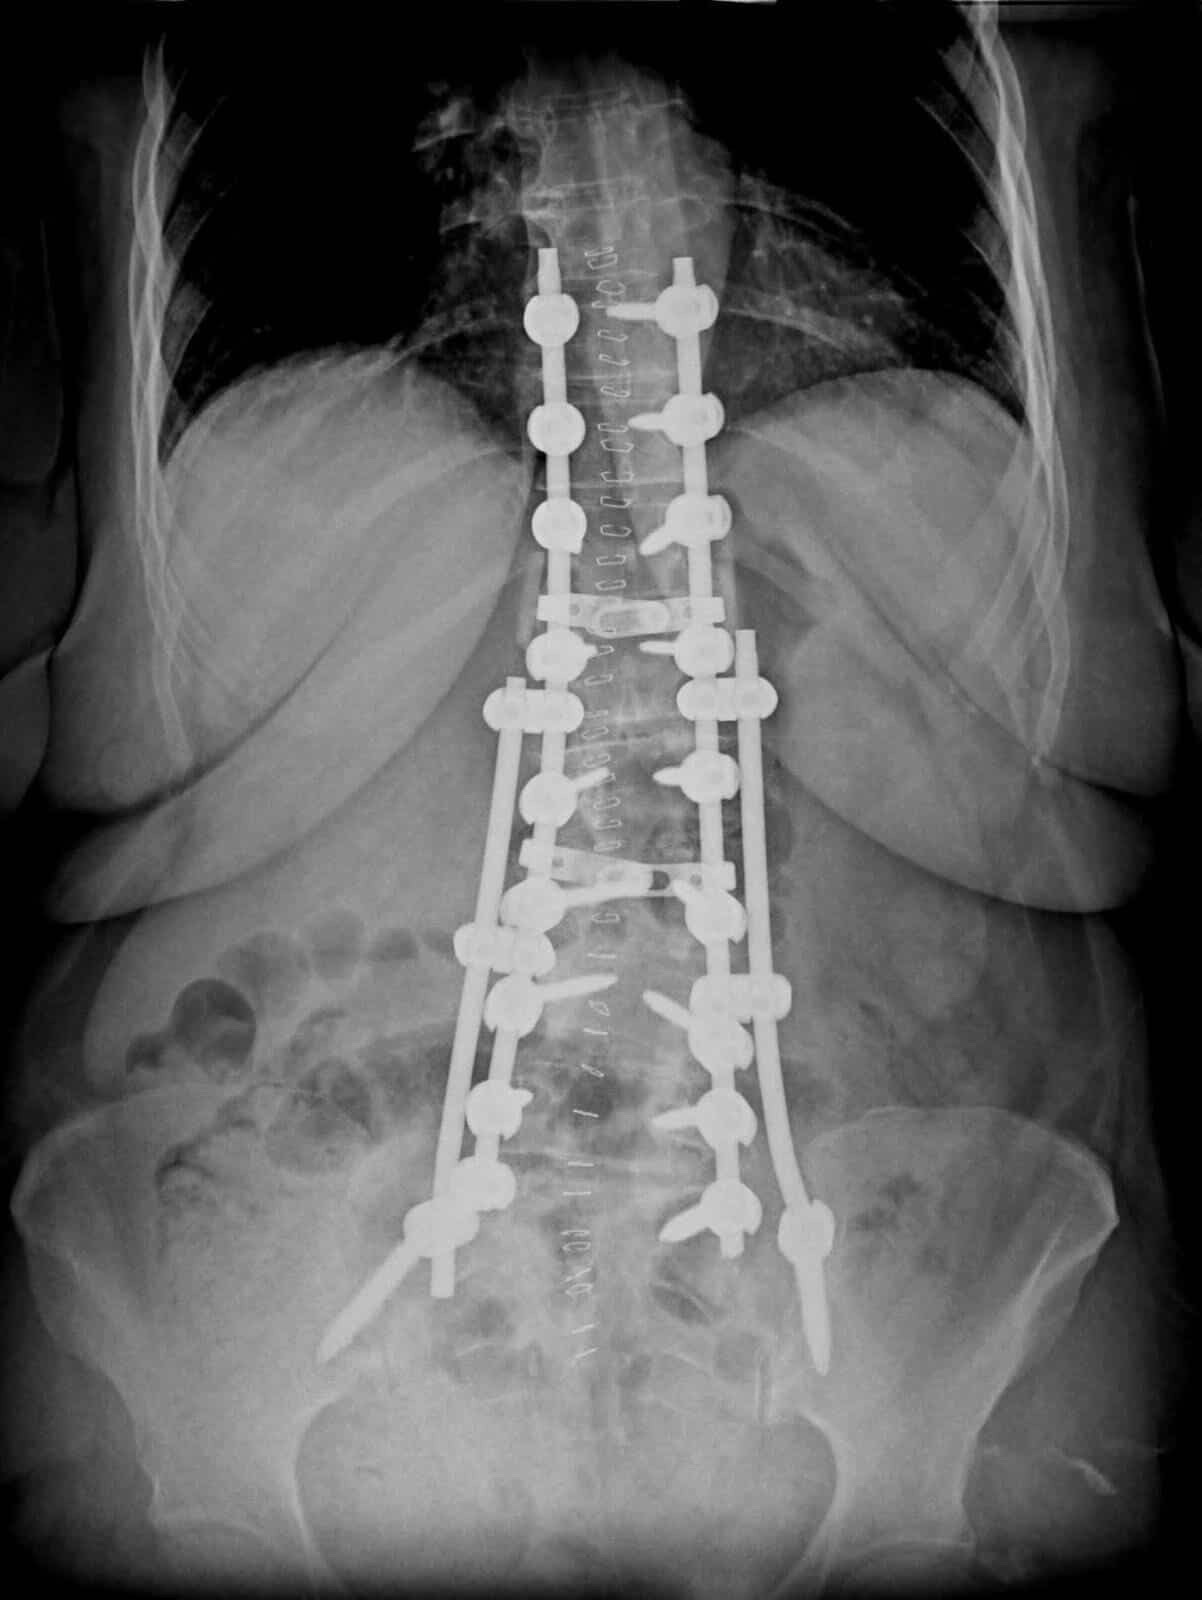

Yapılan tetkik ve değerlendirmeler sonucunda hastaya dejeneratif skolyoz tanısı konulduğunu ifade eden Topal, şu bilgileri paylaştı:“Polikliniğimize bel ve bacak ağrısı, duruş bozukluğu ve yürüme güçlüğü şikâyetleri ile başvuran hastamıza yapılan değerlendirmeler sonucunda dejeneratif skolyoz tanısı konuldu ve cerrahi tedavi planlandı. Ameliyat sırasında omurgada sinirlere baskı oluşturan, kanal daralmasına neden olan disk bozuklukları, kemik dejenerasyonları ve kireçlenmiş yumuşak dokulara müdahale edildi.”

Ameliyat sırasında hastanın omurgasında yaklaşık 30 derece olan eğriliğin 6 dereceye kadar düzeltildiğini belirten Topal, operasyonun ardından hastanın ertesi gün ayağa kaldırıldığını söyledi. Başarılı operasyon sonrası hastanın bel ve bacak ağrılarının belirgin şekilde azaldığı, duruş ve yürüme bozukluğunun düzeldiği ifade edildi. Hasta, yapılan takiplerin ardından taburcu edildi.